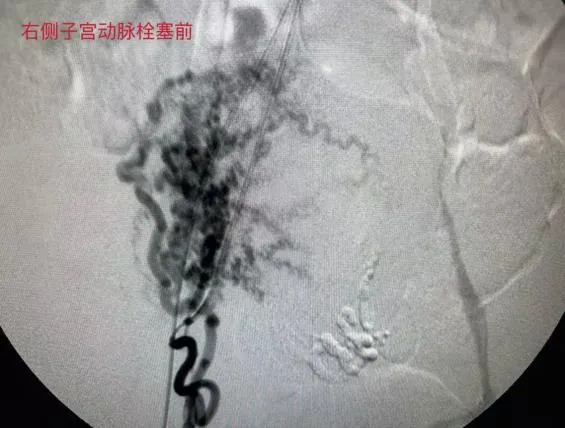

放射影像科主任胡达紧盯着屏幕,手中的导丝精细操作。他需要通过股动脉上一个针尖大小的穿刺点,将导管送到盆腔深处。造影剂注入的瞬间,屏幕上清晰地显示出正在大量出血的动静脉瘘口。

随后,胡达将栓塞剂精准地送入靶血管,迅速封堵这条失控的通道。出血瞬间停止,监护仪上的数字开始趋于稳定。